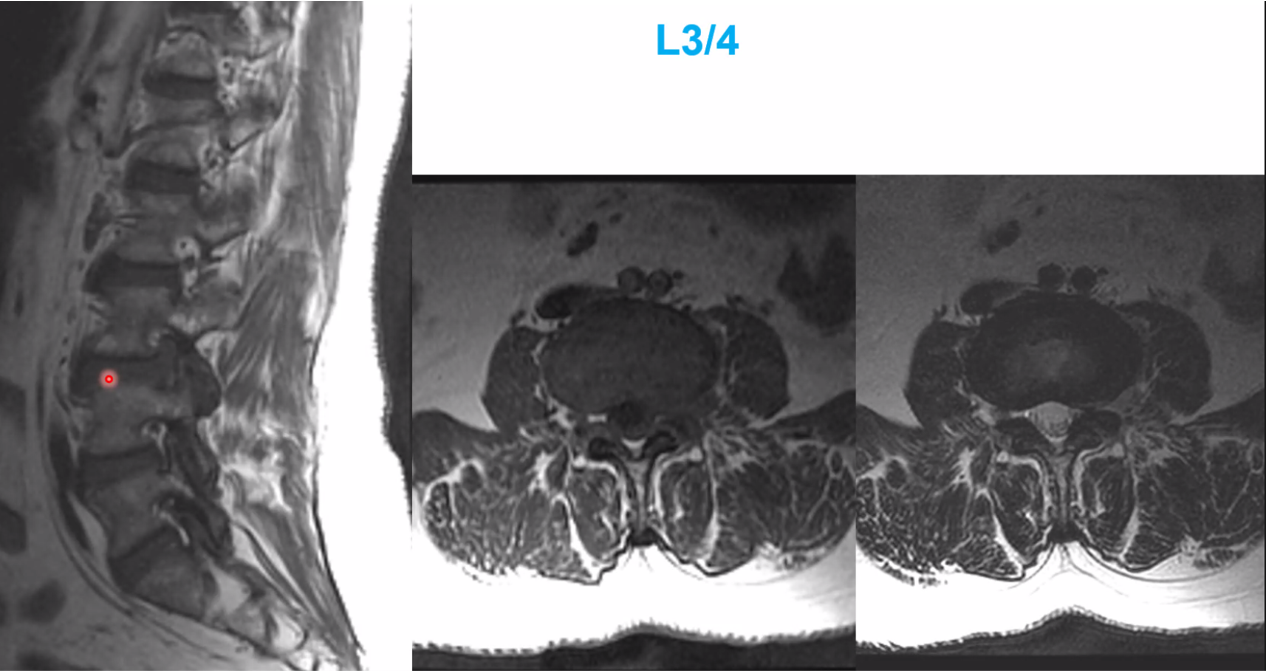

Spinal DAVF will have no flow voids in the cord itself, with have funky serpentine vessels surrounding the cord

spinal avm

notice the flow voids in the spiral cord. Spinal DAVF will have no flow voids in the cord itself, with have funky serpentine vessels surrounding the cord

cav mal in the conus medullaris